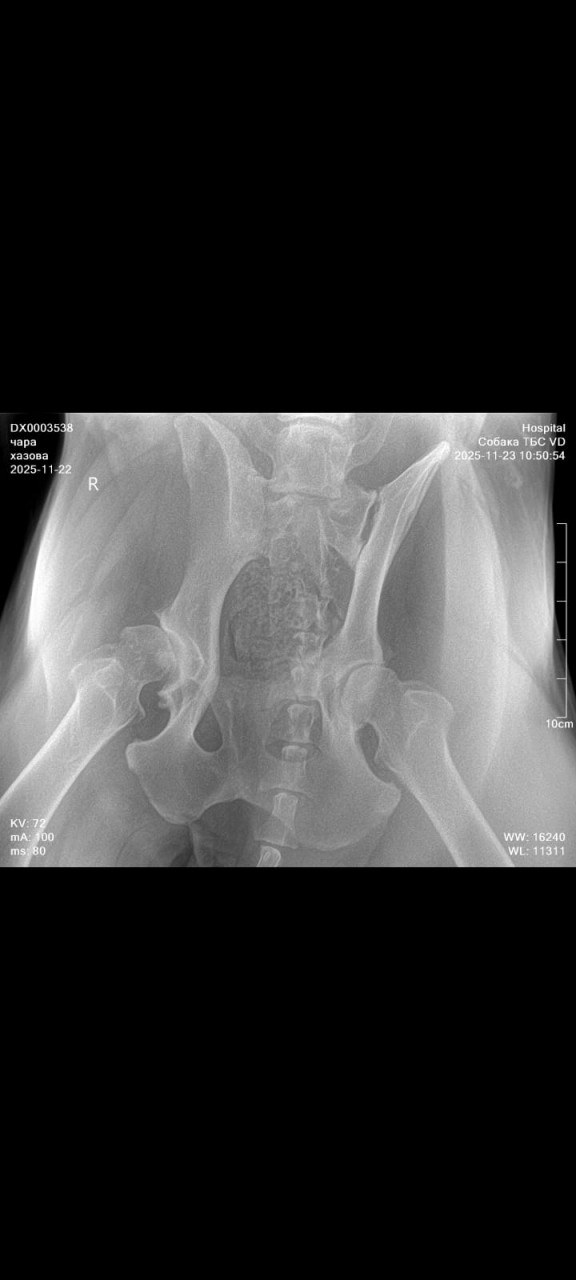

Собака хромает иногда не наступает на лапу сделали рентген что можете сказать по снимку?

Здравствуйте. По снимку видно только общий обзор таза и задних конечностей, но качества недостаточно, чтобы точно оценить суставы, связки или мелкие изменения. Хромота и нежелание наступать на лапу могут быть связаны с суставом бедра, колена или мягкими тканями, но по этому снимку однозначного вывода сделать нельзя. Рекомендую сделать более информативные проекции таза и коленного сустава и показать их ортопеду-ветеринару. Это позволит точнее понять причину хромоты и подобрать лечение.